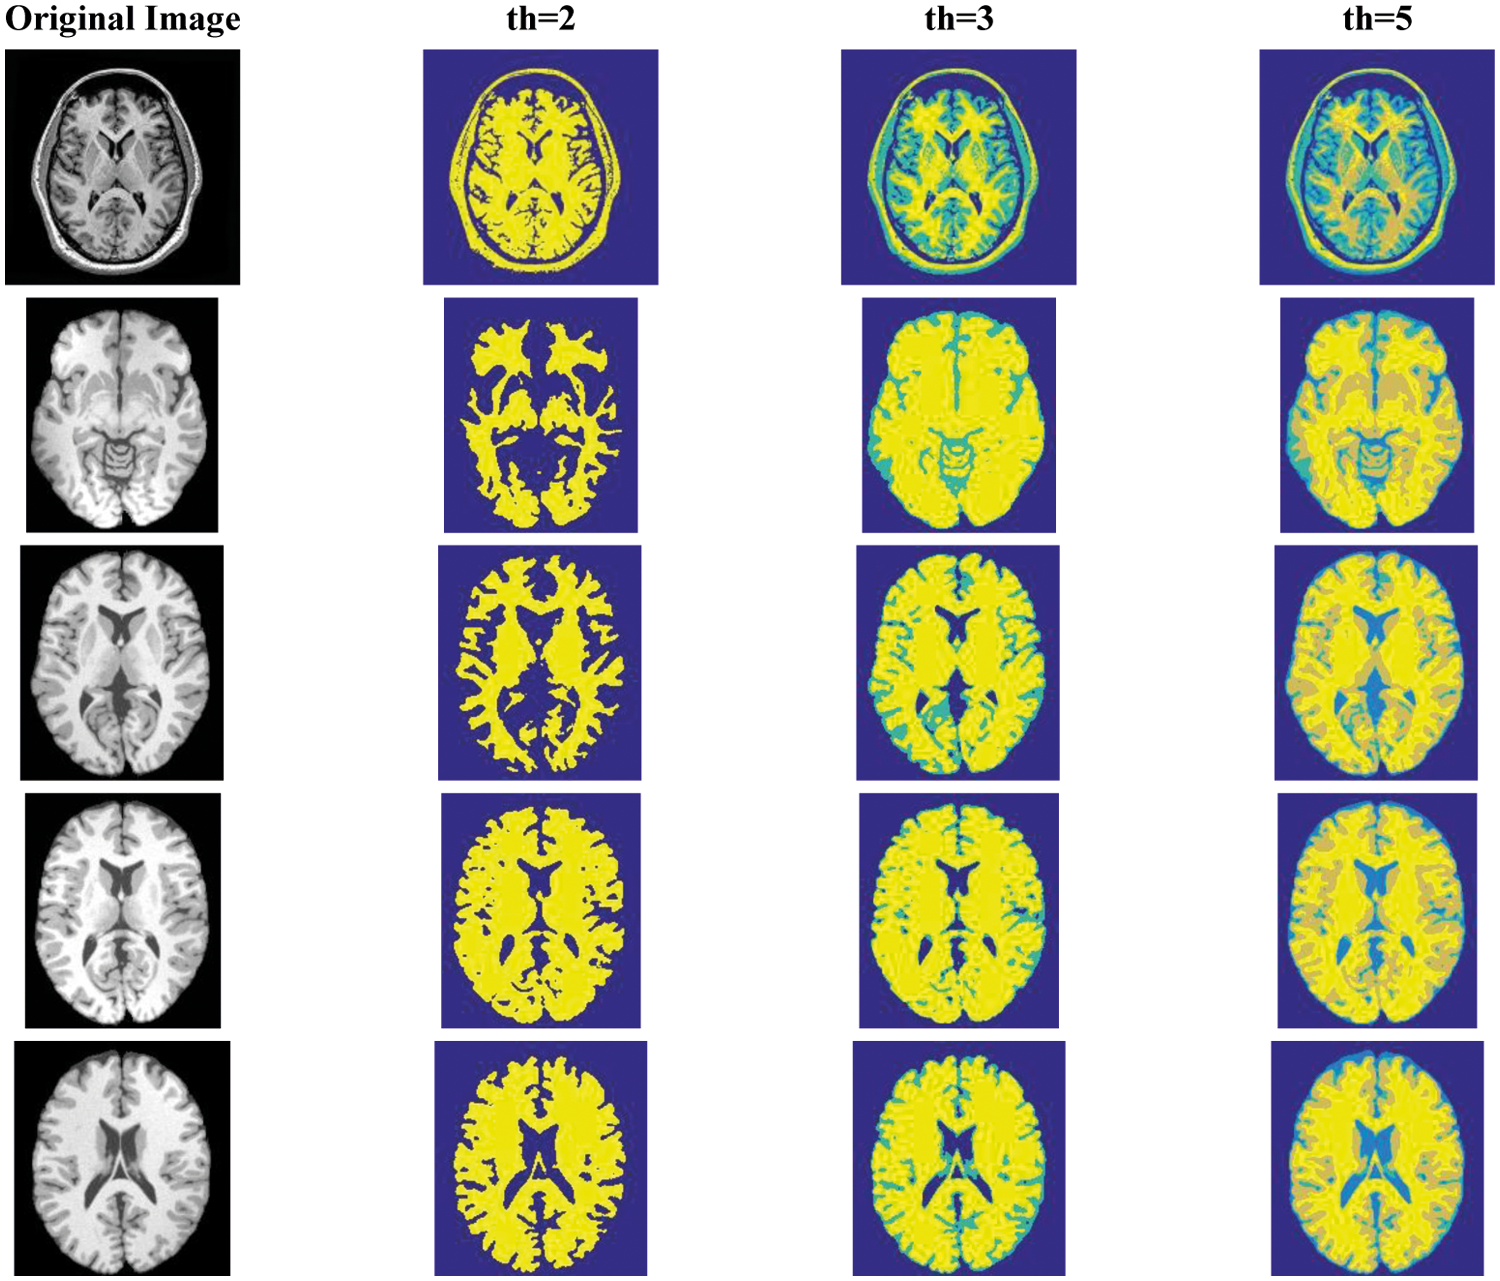

Fig. 4 illustrates five different original brain images and the visual results after thresholding by FHCOA under different threshold conditions. It can be observed from Fig. 4 that as the threshold number increases, the segmentation of the brain image becomes finer, and all parts of the brain tissues gradually converge together. Drawing upon this segmented region, doctors can more effectively focus on a certain region of the brain, which is more conducive to the diagnosis of brain tissue lesions.

At the same time, if the lesion area is not significant enough, we can also add feature analysis and other means to locate it as soon as possible. In order to quantitatively analyze the brain image segmentation effect, Tab. 7 shows the threshold vector, PSNR and FSIM parameter values of FHCOA when the images in Fig. 4 are segmented with different threshold numbers. At the same time, in order to better analyze the effect of FICOA in medical image segmentation, the quantitative segmentation evaluation data of FICOA [22] under the same image conditions are also listed in Tab. 7. From the comparative analysis of FHCOA and FICOA, the PSNR value obtained by FHCOA increased by 0.1371 on average, and the average improvement ratio was 0.628%. The highest increase occurred on Brain 64 image when the threshold number is 3, with an increase value of 0.7746 and a maximum improvement range of 3.916%. In terms of FSIM evaluation indices, FHCOA is slightly better than FICOA, with an average improvement ratio of 0.38%. Based on the above analysis, FHCOA can not only effectively complete the threshold segmentation of normal images, but also realizes the segmentation of brain medical images, which has significant research value.

Figure 4: Medical image thresholding based on FHCOA